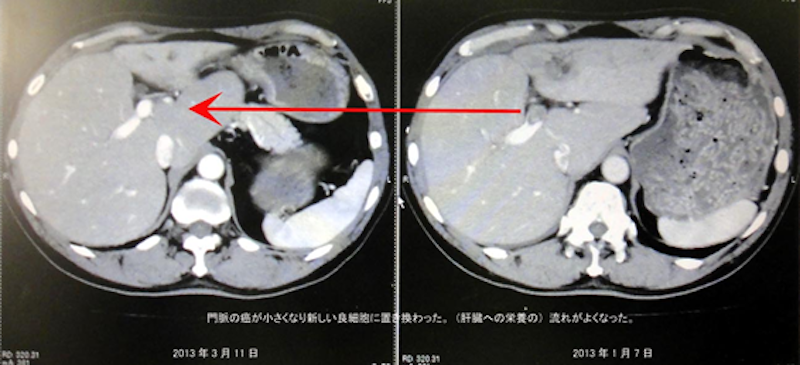

『なんと肝臓の門脈の癌が小さくなるなんて信じられないことが起こったと!!!リンパのガンもわかないぐらい小さくなった』との驚くようなご報告をいただきました。

見た感じではガンが消えているように感じます。ガンが小さくなって正常な細胞に変化してきているようです。病院の先生方も不思議がられています。